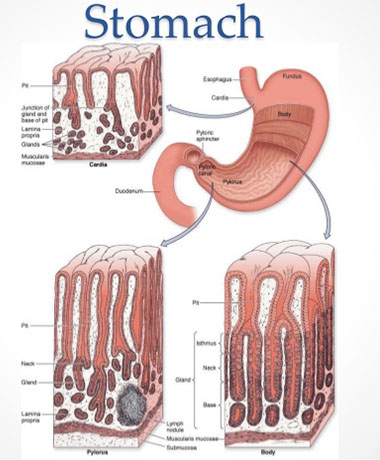

Stomach

Stomach embryology

Made of endoderm, the stomach starts as foregut dilation, and is fully developed by parturition.

Rugae/ mucosa of different zones (cardiac, fundus, body, antrum, and pylorus) appear grossly different, depending on distentiability.

- Areae gastricae - slight indentations in mucosa; grossly visible

Stomach Anatomy

Four parts: Cardia, fundus, body, and pylorus

- has lots of rugae if not distended

Cardia - opens from the esophagus, at level of T11

- lined c mucin-secreting foveolar cells forming small glands

Fundus - dilated superior portion; have chief cells (make pepsin)

- cardial notch bwt esophagus and fundus

Body (corpus) - largest part of stomach bwt fundus and pylorus

Pylorus / Antrum - goes from pyloric antrum to pyloric canal to pyloric sphincter

- lined c mucin-secreting foveolar cells forming small glands, also have endocrine cells (G cells) to stim luminal acid secretion by parietal cells in fundus and body

Most of vascular supply comes from aorta: right and left gastric arteries and right and left gastro-epiploic (gastro-omental) arteries anastamose along greater and lesser curvatures, respectively

- fundus gets blood from short and posterior arteries

Stomach Histology

Basically two types of epithelium in stomach:

1. Oxyntic type

- Has chief cells (blue chief [are more acidic]) and parietal cells (pink parietal, are basic because secrete acid)

- Have a thin foveolar region and thicker glandular region

2. Antral type

- Have thicker foveolar region, the foveolar region and glandular region sizes are ~50/50% of the epithelial thickness

- Secretes mucous and doesn't have chief and parietal cells

6 major cell types: (1) Mucous neck cells, (2) Parietal cells (oxyntic cells), (3) Chief cells (peptic cells), (4) Stem cells, (5) Enterochromaffin cells (gastroendocrine cells) (6) foveolar cells

(1) Mucous neck cells - oval nuclei c mucus in apical droplets

- different from goblet cells

(2) Parietal cells (oxyntic cells) - MC in upper part of body of gastric gland, separated by chief cells, have lots of mitochondria

- secrete hydrochloric acid and intrinsic factor (IF)

(3) Chief cells (peptic cells) - MC in lower part of gastric gland, apical portion has secretory granules c pepsinogen, stimulated by acetylcholine

- uncommon in antrum or pylorus

(4) Stem cells - adjacent to neck region, continuously renew gastric mucosa; can migrate anywhere in gland to replace necessary cells

(5) Enterochromaffin cells (gastroendocrine cells) - has apical nucleus and light cytoplasm; produce peptide hormones

- member of the Diffuse Neuroendocrine System (DNES)

(6) Foveolar cells - line entire stomach; secrete mucin, appear magenta to pink on PAS

- there is no "foveolar mucosa", just oxyntic (has chief cells) or antral-type (mucous-secreting)

- the duodenum can have "foveolar metaplasia"

Wall levels: 1) Mucosa, 2) Submucosa, 3) Muscularis propria, and the 4) Serosa

- (2)-(4) same throughout GI

Mucosa

- homogenous pattern throughout stomach, covered in mucus, and contains highly intertwined glands

4 gland parts: (1) Foveola (gastric pit) (2) isthmus (3) neck (4) body

(1) Foveolae (gastric pits): microscopic invaginations that receive glandular secretions at their bases, lined by foveolar (mucous) cells

-- Lamina propria separates foveolae / glands

-- entry (cardiac) and exit (pylorus) tissue has lots of mucus glands, and has wider foveolae (villous appearance) and deeper foveolae (~50% of cariac/pyloric mucosal thickness) and lamina propria thick

- between mucosal regions of the cardia and pylorus in the body and fundus, glands secrete more pepsin and acid

(2) Isthmus - in the body and fundus made of mostly parietal cells (oxyntic cells), but also has mucous neck cells

- endocrine cells in the deep part of isthmus towards neck / base

(3) Neck - narrow portion of gland underneath fovealar region;

- has mucous cells (MC cell type), parietal cells and stem cells

(4) Body / base - majority of length of gland

- parietal cells MC in upper portion, are separated by chief cells

- chief cells MC in lower (end) portion, and has apical granules with pepsinogen

Lamina propria should not have too many lymph and / or plasmas; neutrophils should not be in mucosal epithelium or lamina propria, though eos are a normal part of the lamina propria

- these inflammatory components more prominent in intestines

Difference of stomach histology by region:

Cardiac and antral type versus fundus and body type

- cardiac and antrum protect esophagus and (from) duodenum (respectively); is made mostly of mucous cells, though the antrum also has G (gastrin-makin) cells not seen in cardia (or in body or fundus for that matter)

-- in atrophic gastritis can see "antralized" body and / or fundus with G cells

- Fundus and body make the acids / enzymes